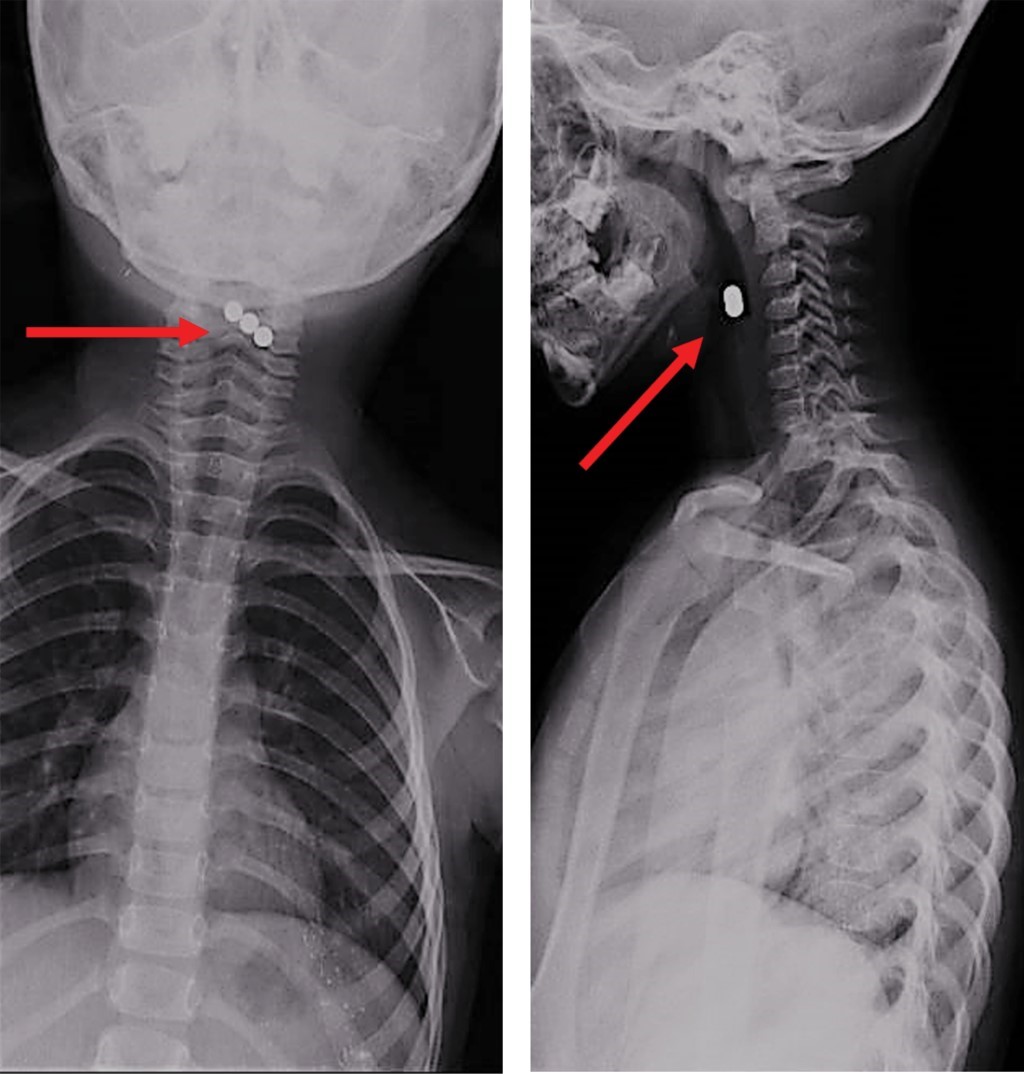

Se trata de paciente femenino de tres años y 11 meses, sin antecedentes de importancia, que refiere ingestión accidental de 17 imanes 28 horas antes del inicio de los síntomas. Presenta disfagia y odinofagia, se toma radiografía simple de tórax que muestra tres imanes localizados en faringe (Figura 1). En la placa de abdomen se observan los 14 imanes restantes (Figura 2). Fue enviada a nuestro hospital para ser evaluada por un servicio de Endoscopía.

Figura 1

Figura 2